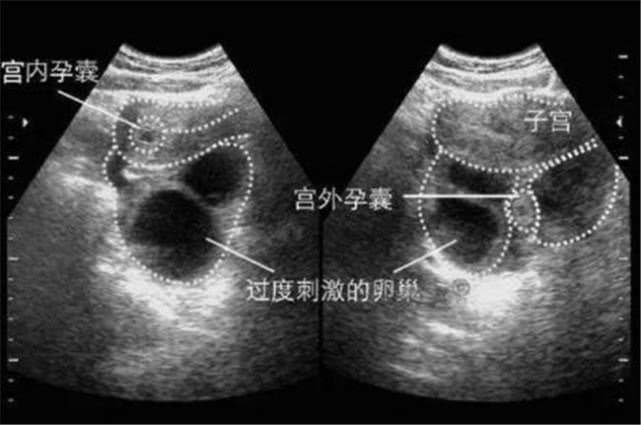

宫外孕顾名思义就是精子与卵子结合的场所没有在子宫里,反而在输卵管外面着床,很容易引起大出血以及胎死的现象,因此作为女人应该重视与预防。